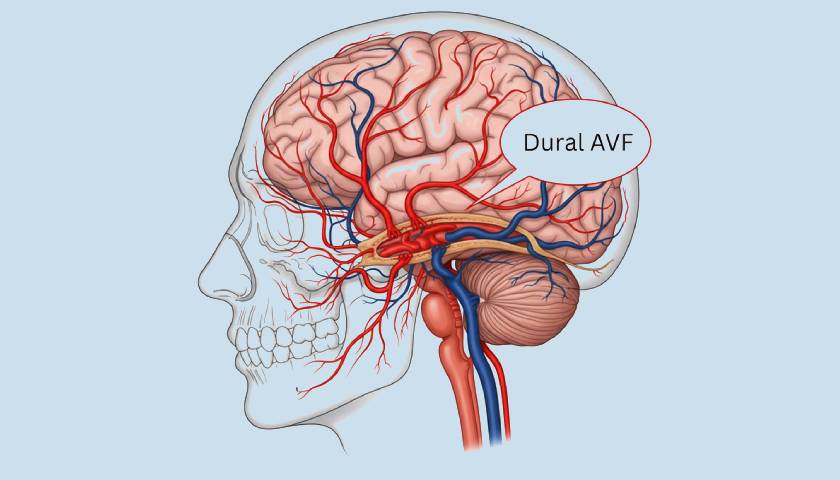

धमनीशिरापरक फिस्टुला (एवीएफ) क्या है?

एक धमनीशिरापरक फिस्टुला (एवीएफ) एक धमनी और एक नस के बीच एक असामान्य संबंध है। एक स्वस्थ प्रणाली में, रक्त केशिकाओं के माध्यम से धीरे-धीरे बहता है। एवीएफ में, रक्त इन केशिकाओं को बायपास करता है और उच्च दबाव पर सीधे नसों में बहता है।

यह असामान्य परिसंचरण कर सकता है:

- अधिभार नसें

- ऊतकों को ऑक्सीजन वितरण कम करें

- समय के साथ पोत क्षति का कारण बनता है

- रक्तस्राव, तंत्रिका क्षति, या हृदय तनाव का कारण बनता है